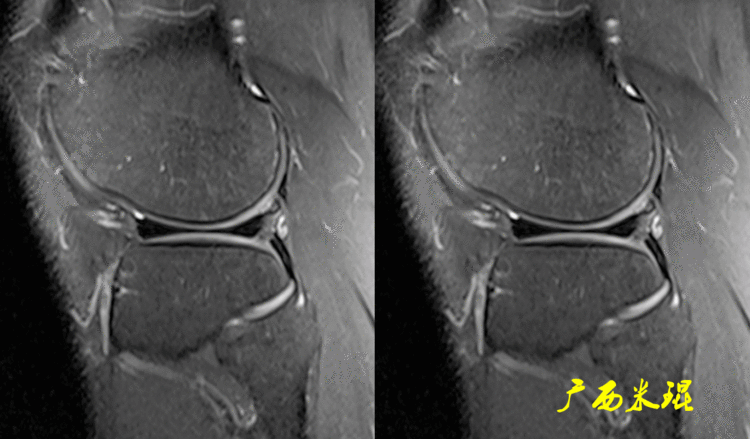

(1)假桶柄MR冠状位上偏后的层面,“C”形或“O”形的内外侧半月板偏后侧层面有可能同时扫描到半月板体部和后角,容易误诊为桶柄状撕裂,而矢状位或横断位上半月板形态是正常的。

下面这张MR冠状位显示为内侧半月板后角的假桶柄,其母体(图片中内侧的那一部分半月板)并没有变小、形态及信号均正常。

下面这张MR冠状位显示为外侧半月板后角的假桶柄,尽管在髁间窝发现半月板信号,但其母体(图片中外侧的那一部分半月板)并没有变小、形态及信号均正常。